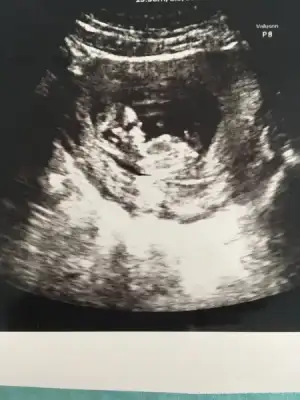

valla bana 10+2 de kız olabilir dedi.12+6 da kesin erkek dedi Can'ım hatta pipi nin çıktısını bile verdi.

Eklentiler

• image.webp

image.webp

13,2 KB · Görüntüleme: 88